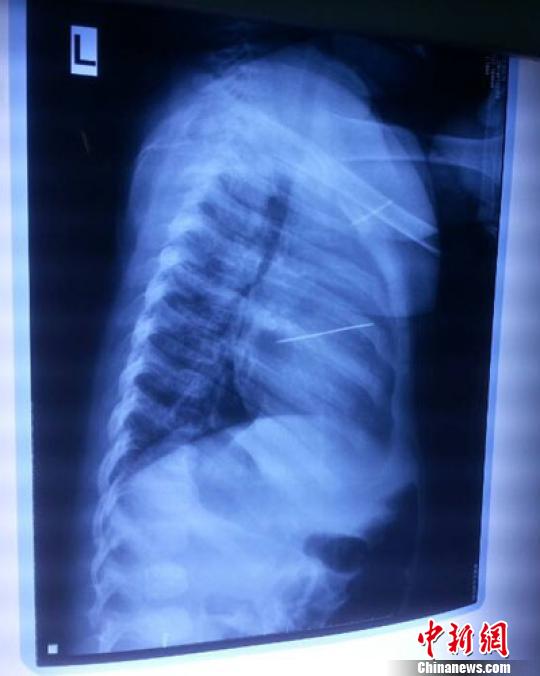

女嬰胸片提示心臟里面扎了一個(gè)縫衣針 蔡迅翔 攝

醫(yī)院胸心外科主任翟波介紹說,1月22日,小患者彤彤因?yàn)榘l(fā)燒抽搐來(lái)醫(yī)院就診,常規(guī)檢查時(shí)發(fā)現(xiàn)孩子心臟里面扎了一個(gè)縫衣針。

“第二天上午,我們做了個(gè)緊急彩超檢查,發(fā)現(xiàn)針是從患者右心室表面刺入,穿破室間隔,到達(dá)左心房,中間還有一部分損害到二尖瓣。于23號(hào)下午,我們就做了一個(gè)緊急手術(shù),手術(shù)中發(fā)現(xiàn),這枚針已經(jīng)刺入心臟,沒入了右心室的下面,表面已經(jīng)看不到針了,僅能看到一個(gè)小針眼,還在往外滲血,一點(diǎn)一點(diǎn)的滲,心包腔里面大概有100多毫升的出血,心包上一個(gè)洞,針在右心室表面刺入以后,穿過室間隔,在二尖瓣的上方,進(jìn)入了左心房,在針的四周,有很多纖維沉積物,包繞著這枚針。”翟波說,他們把針取出來(lái)以后,測(cè)量了一下,長(zhǎng)度大概是五厘米,同時(shí)發(fā)現(xiàn)這個(gè)針給患者左心房的后壁造成了一定的損傷,左心房的后壁已經(jīng)損傷了三分之二,還剩下有左心房的外膜,很薄的一層,如果這一層再破的話,這個(gè)孩子將會(huì)引起大出血,很快就會(huì)死亡。